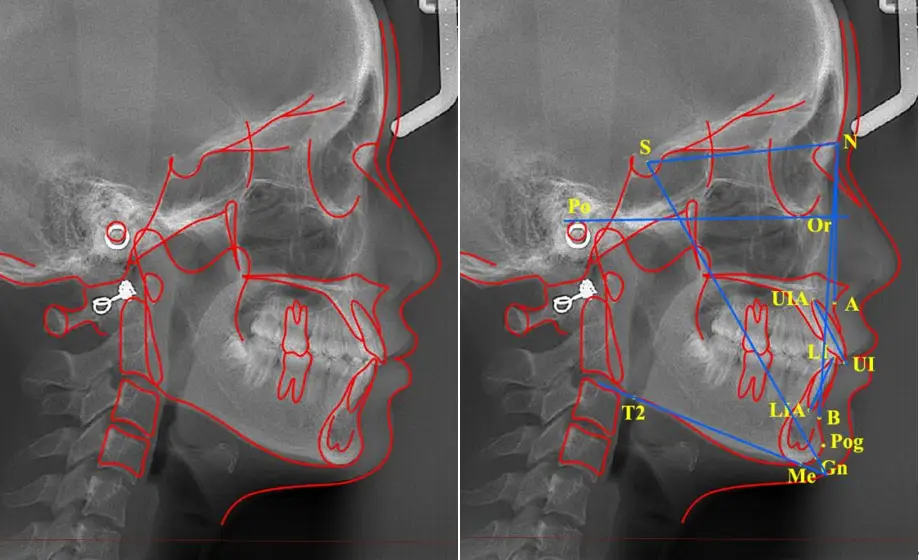

AI头影测量分析功能上线!按病例收费,每个病例付费分析一次生成数据之后,可以随时查看。

AI头影测量分析功能上线!按病例收费,每个病例付费分析一次生成数据之后,可以随时查看。